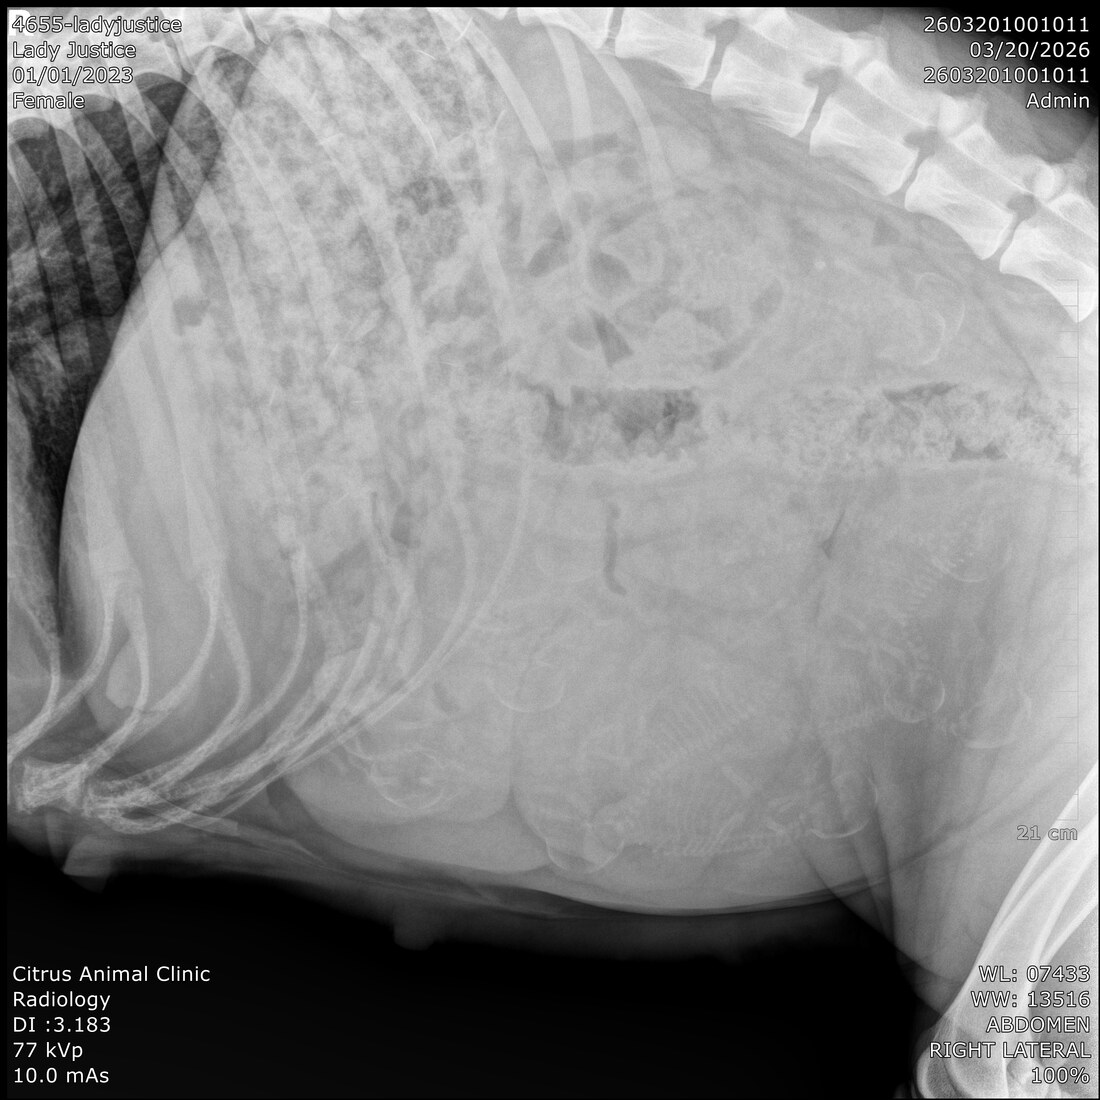

Lady Justice XVII

(Justice)

Sex:

Female

Date of Birth:

April 4th, 2023

Sire:

Kaiczar Ezekiel Zlovestny Vom Nocnihlidka

Dam:

Cora Vina-Dog Slovakia

Owner:

Mike Walker